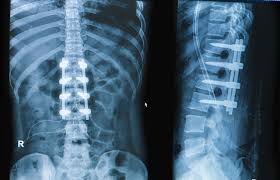

Spine fusion surgery is a specialized procedure that permanently connects two or more vertebrae in the spine, eliminating motion between them. This helps stabilize the spine, relieve pain, and correct deformities caused by conditions such as degenerative disc disease, spondylolisthesis, scoliosis, or spinal fractures. During the surgery, bone grafts or implants are placed between the affected vertebrae to promote fusion. Over time, the bones heal together, creating a single, solid structure. This procedure is particularly beneficial for patients with severe spinal instability or chronic back pain that doesn’t respond to non-surgical treatments.

At Indian Spine Clinic, Dr. Mohammed Faizan performs spine fusion surgery using the most advanced techniques to ensure accuracy and safety. Depending on the patient’s diagnosis, he may use minimally invasive or traditional open approaches. Modern instrumentation, such as screws, rods, or cages, is used to stabilize the spine while bone grafts facilitate fusion. The procedure is performed under high-definition imaging and navigation guidance for maximum precision. This technology ensures minimal tissue disruption, reduced blood loss, and faster postoperative recovery.